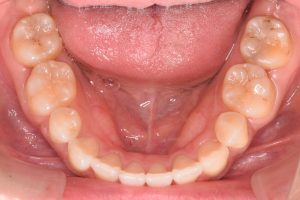

下から

下あご